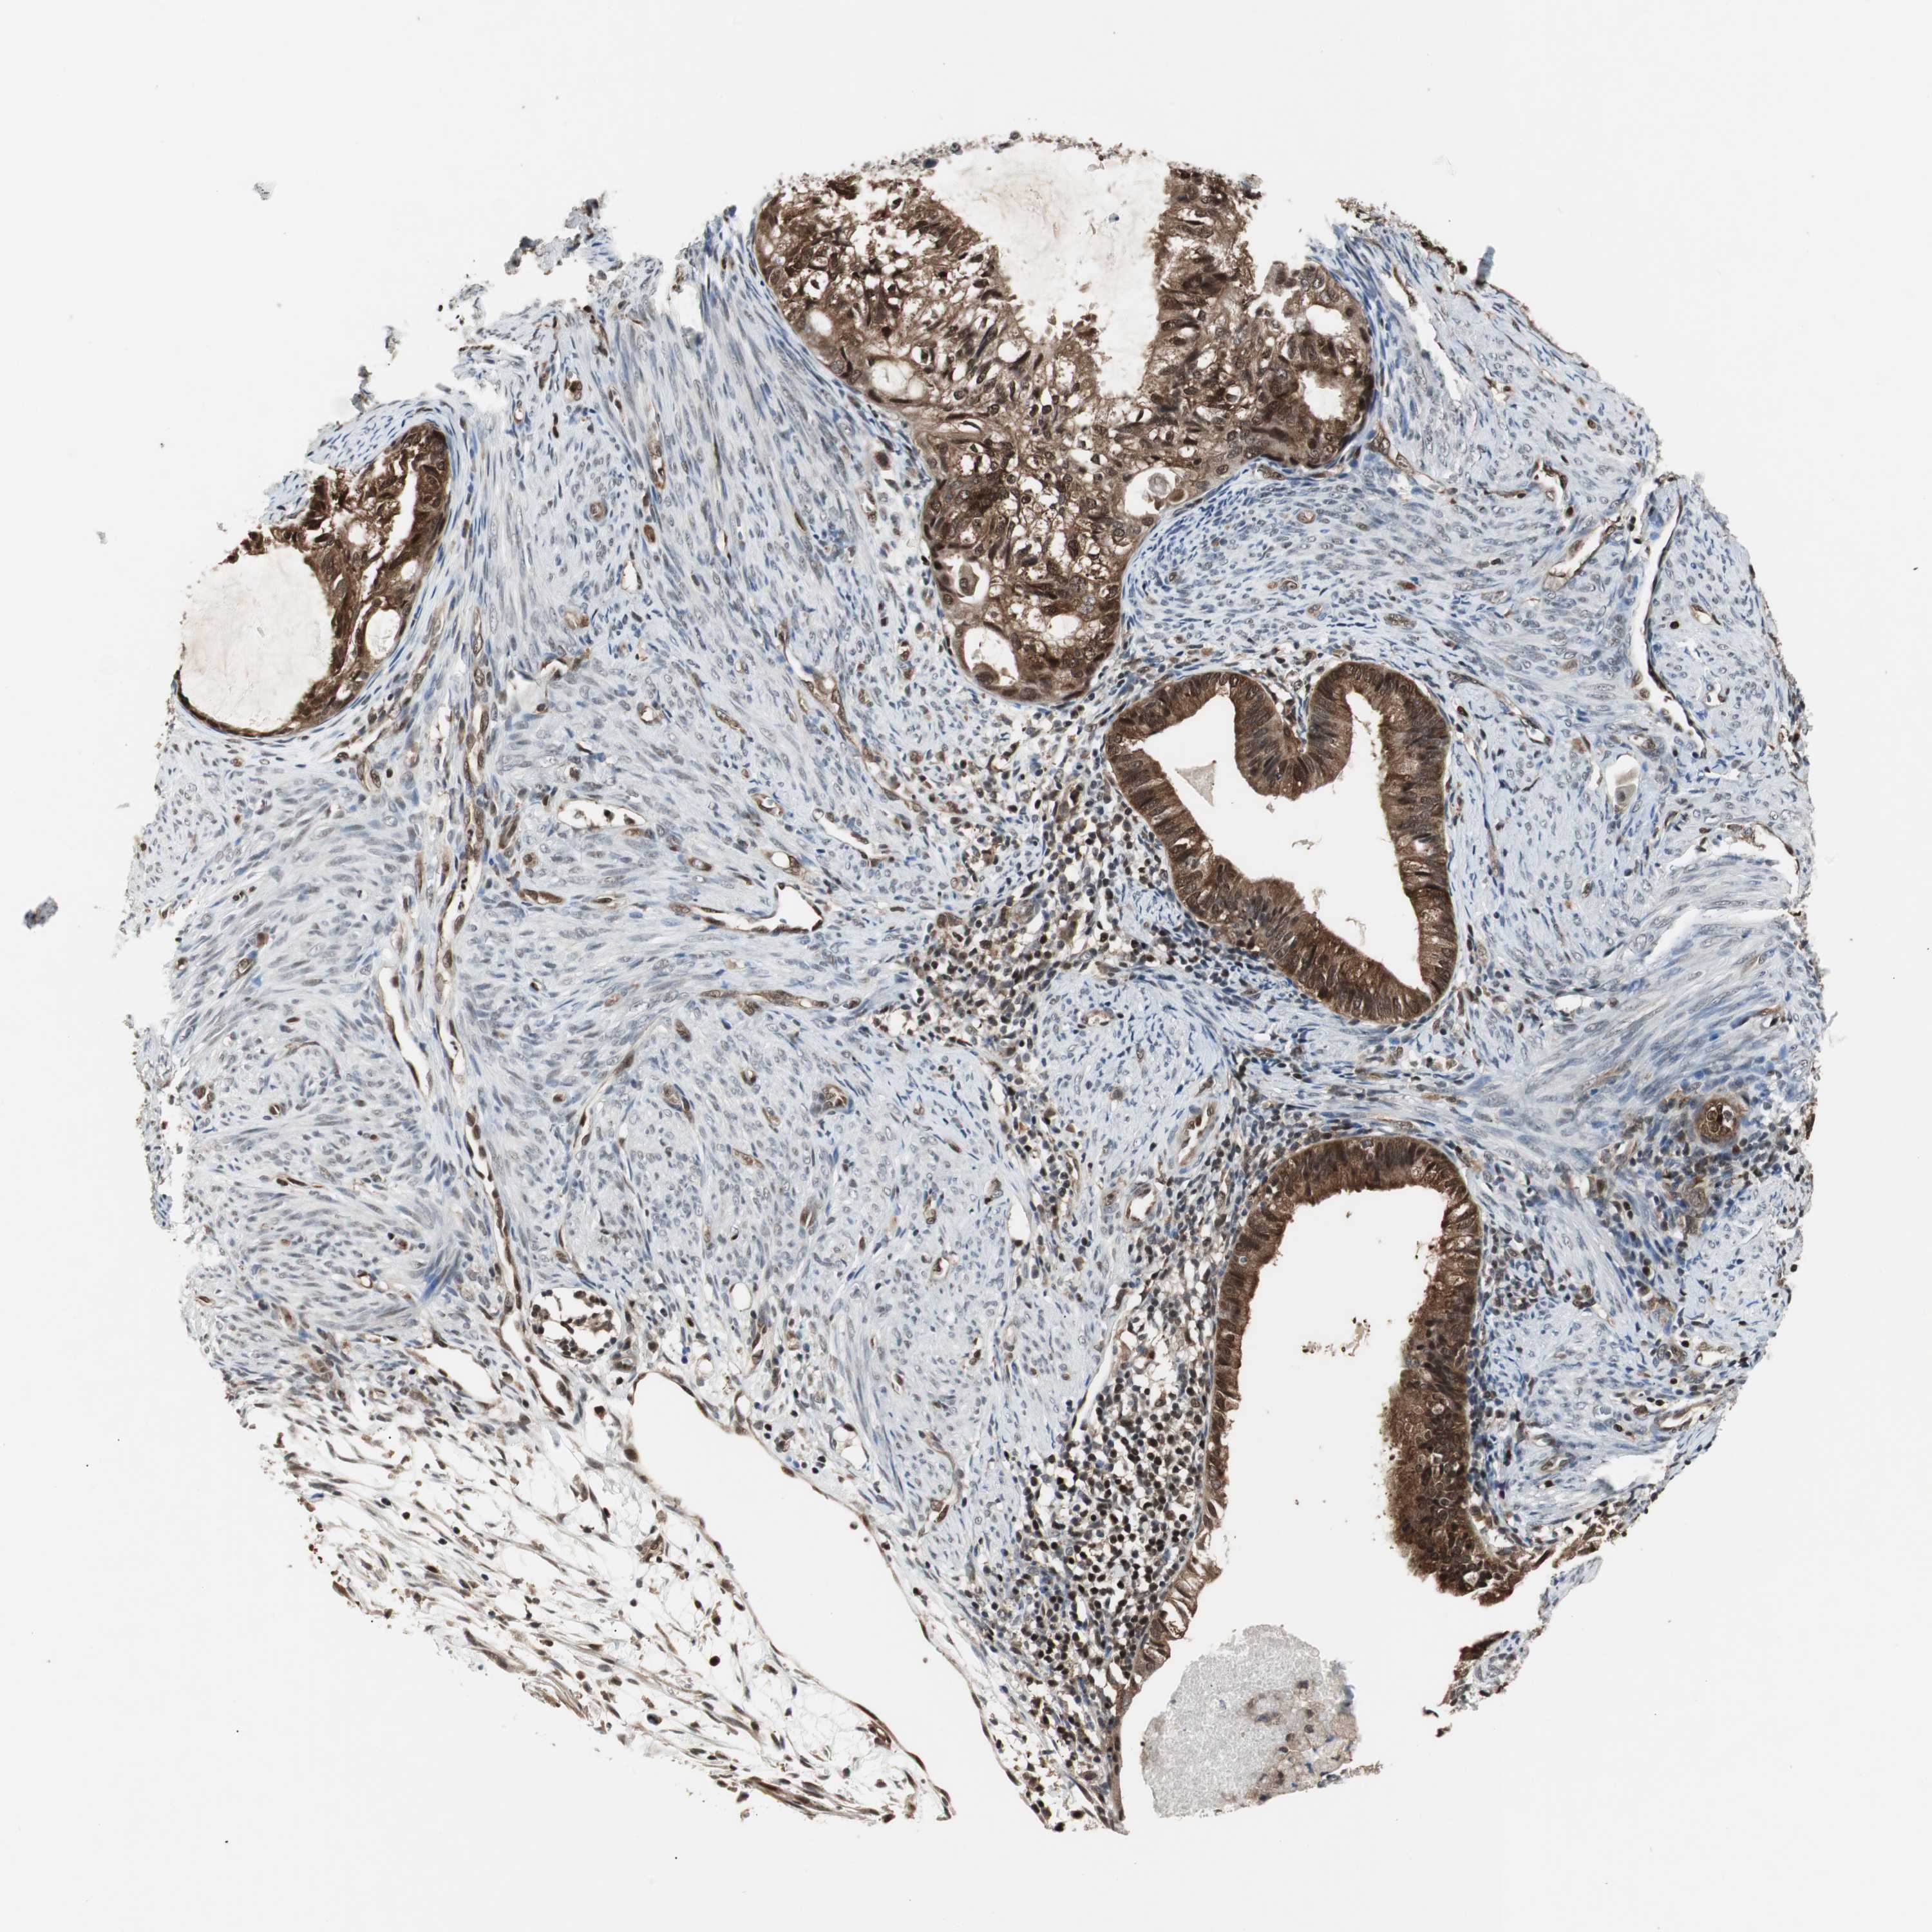

CERVICAL CANCER - Protein expressioni

A mouse-over function shows sample information and annotation data. Click on an image to view it in a full screen mode. Samples can be filtered based on level of antibody staining by selecting one or several of the following categories: high, medium, low and not detected. The assay and annotation is described here.

Note that samples used for immunohistochemistry by the Human Protein Atlas do not correspond to samples in the TCGA dataset.

Antibody stainingi

Antibody staining in the annotated cell types in the current human tissue is reported as not detected, low, medium, or high, based on conventional immunohistochemistry profiling in selected tissues. This score is based on the combination of the staining intensity and fraction of stained cells.

Each image is clickable and will lead to virtual microscopy that enables deeper exploration of all samples and also displays staining intensity scores, fraction scores and subcellular localization as well as patient and tissue information for each sample.

HPA022434

HPA022953

HPA022959

HPA028758

CAB007783

Staining

High

Medium

Low

Not detected

Intensity

Strong

Moderate

Weak

Negative

Quantity

>75%

75%-25%

<25%

None

Location

Nuclear

Cytoplasmic/membranous

Cytoplasmic/membranous,nuclear

Squamous cell carcinoma, NOS

Adenocarcinoma, NOS